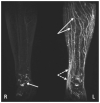

Background: Clinical examination and lymphoscintigraphy are the current standard for investigating lymphatic function. Magnetic resonance imaging (MRI) facilitates three-dimensional (3D), nonionizing imaging of the lymphatic vasculature, including functional assessments of lymphatic flow, and may improve diagnosis and treatment planning in disease states such as lymphedema.

Results: From 612 identified articles, 43 articles were included and their protocols and results summarized. Field strength was 1.5 or 3.0 T in all studies, with 25/43 (58%) employing 3.0 T imaging. Most commonly, imaging of the peripheries, upper and lower limbs including the pelvis (32/43, 74%), and the trunk (10/43, 23%) is performed, including two studies covering both regions. Imaging protocols were heterogenous; however, T2 -weighted and contrast-enhanced T1 -weighted images are routinely acquired and demonstrate the lymphatic vasculature. Edema, vessel, quantity and morphology, and contrast uptake characteristics are commonly reported indicators of lymphatic dysfunction.